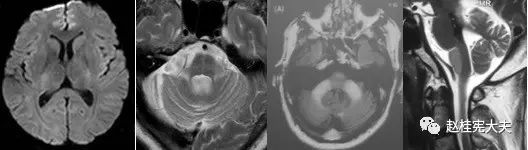

重要申明:以下每个部分会配磁共振图片,因疾病和影像之间存在同病异象、同像异病,为避免误导,图片不标注疾病,请各自鉴赏,另其中有部分图片来源于网络,有疑问可与本人联系。

I--infection,感染

指的是各种感染,病毒(单纯疱疹病毒、带状疱疹…)、细菌(革兰阳性、革兰阴性、球菌、杆菌…)、结核、。真菌、梅毒、各种寄生虫(囊虫、弓形虫、吸虫、裂头蚴等)。还有进行性多灶性白质脑病(PML)、CJD、Whipple’s 病等。亚急性细菌性心内膜炎。